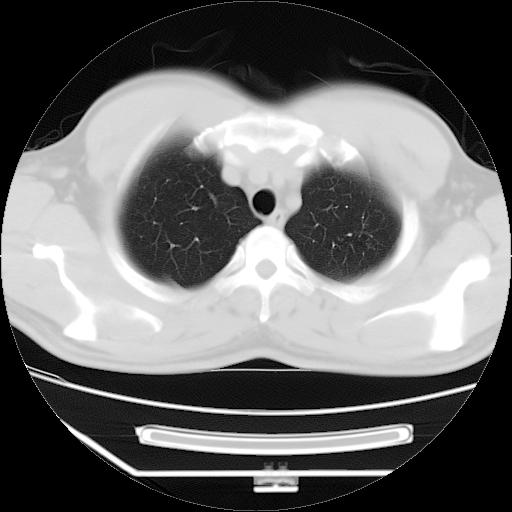

标题: CT21560:胸部肿块影,请会诊

男,38岁,于2009年8月9日晚突发左侧胸痛,今x线提示左下肺阴影,为了明显确诊断,行ct检查,

血常规:嗜酸性细胞增高,单核细胞增高。

病灶发生在下叶,密度均匀,边缘模糊、毛糙,周围血管纹理增强扭曲改变,靠近胸膜处病灶胸膜反应明显。

支持考虑---球形肺炎。

左肺舌叶病变。主体病灶呈类圆形中心密度低,成液化趋势周边班片影分布

考虑肺脓肿